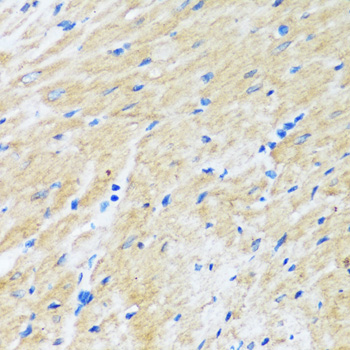

Bcl-2, Polyclonal Antibody (Cat# AAA30544)

Bcl-2, Polyclonal Antibody (Cat# AAA31360)